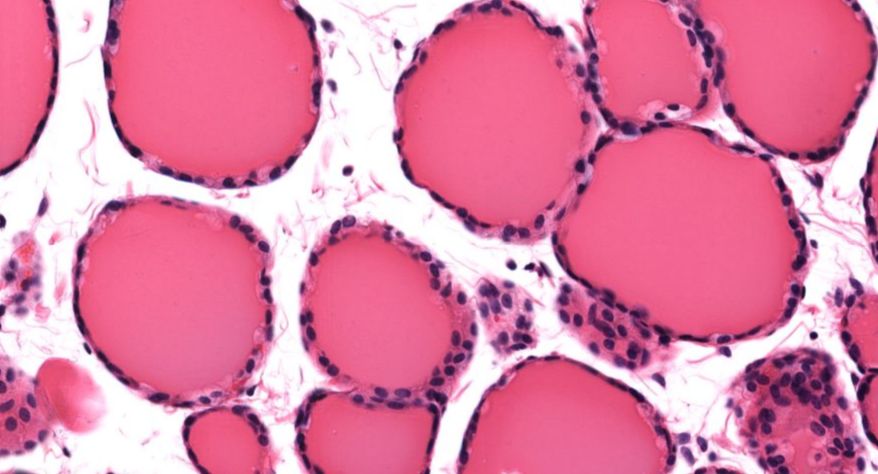

低倍镜观察:1. 被膜:由薄层结缔组织组成。2. 实质:由许多大小不等的滤泡构成。滤泡壁是单层立方上皮细胞,滤泡腔内充满粉红色匀质胶状物,滤泡之间的结缔组织内有丰富的血管。高倍镜观察:1. 滤泡:滤泡壁的单层滤泡上皮细胞一般呈低柱状或立方状,胞质着浅色,细胞核呈圆形。滤泡腔内充满了粉红色匀质胶质。2. 滤泡旁细胞:体积较大,呈圆形或椭圆形;细胞核较大,呈圆形,着色较浅,细胞质染色也较浅。细胞或嵌在滤泡壁上或成团分布于滤泡之间。3. 间质:由结缔组织组成。位于滤泡之间。其中含有丰富的毛细血管及三五成群的滤泡旁细胞。

1.全景图

![]()

2.滤泡

3.滤泡上皮细胞

4.胶质

5.滤泡旁细胞1

7.滤泡旁细胞2